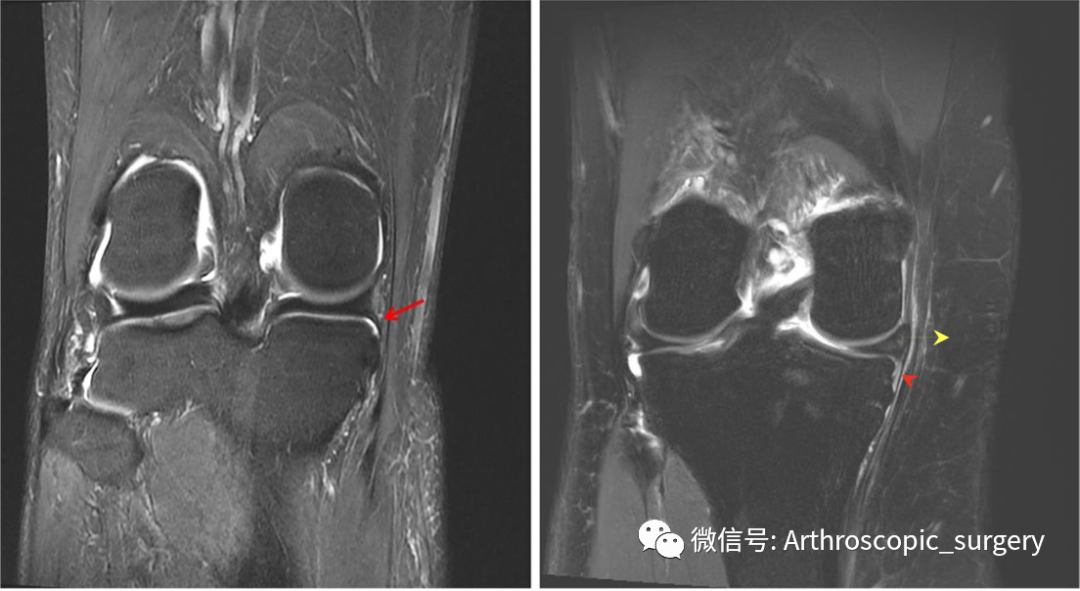

冠状位MRI显示板胫韧带损伤。术前冠状位MRI显示内侧板胫韧带完整(左,箭头),板胫韧带损伤(右,红色箭头),半月板外凸(右,黄色箭头)